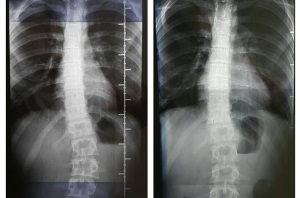

Сколиоза е деформация на гръбначния стълб, която се среща и при здрави деца и най-често е с неизвестна причина (идиопатична). Изкривяването на гръбнака засяга всичките три равнини и е последвано от мускулна дисфункция и намален капацитет на белите дробове. Асиметричното натоварване на гръбнака е един от факторите за бързата прогресия на сколиозата. Чрез него сколиотичната кривина се оказва под голям натиск, причинен от промяната в баланса на тялото в изправено положение.